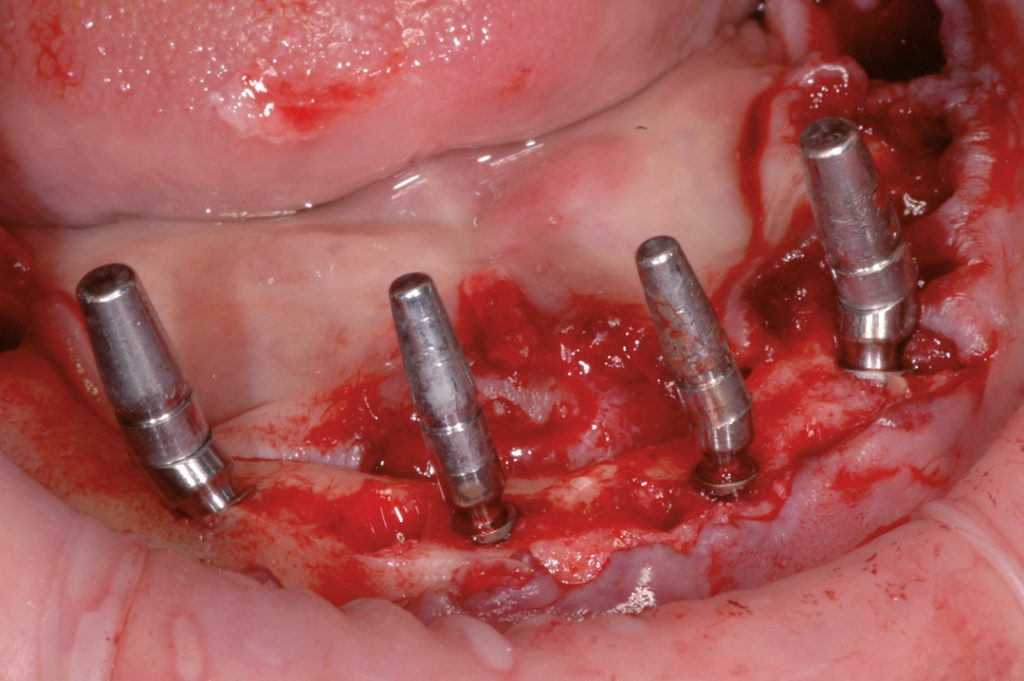

Se reposicionan los transferes sobre los MUA, cierre de la herida con suturas reabsorbibles

Cierre de la herida con suturas reabsorbibles para tomar la impresión a nivel del implante con material de silicona

Pilares in situ antes de la colocación de los tornillos de cicatrización sobre los pilares, impresión, se envían transferes y análogos al laboratorio